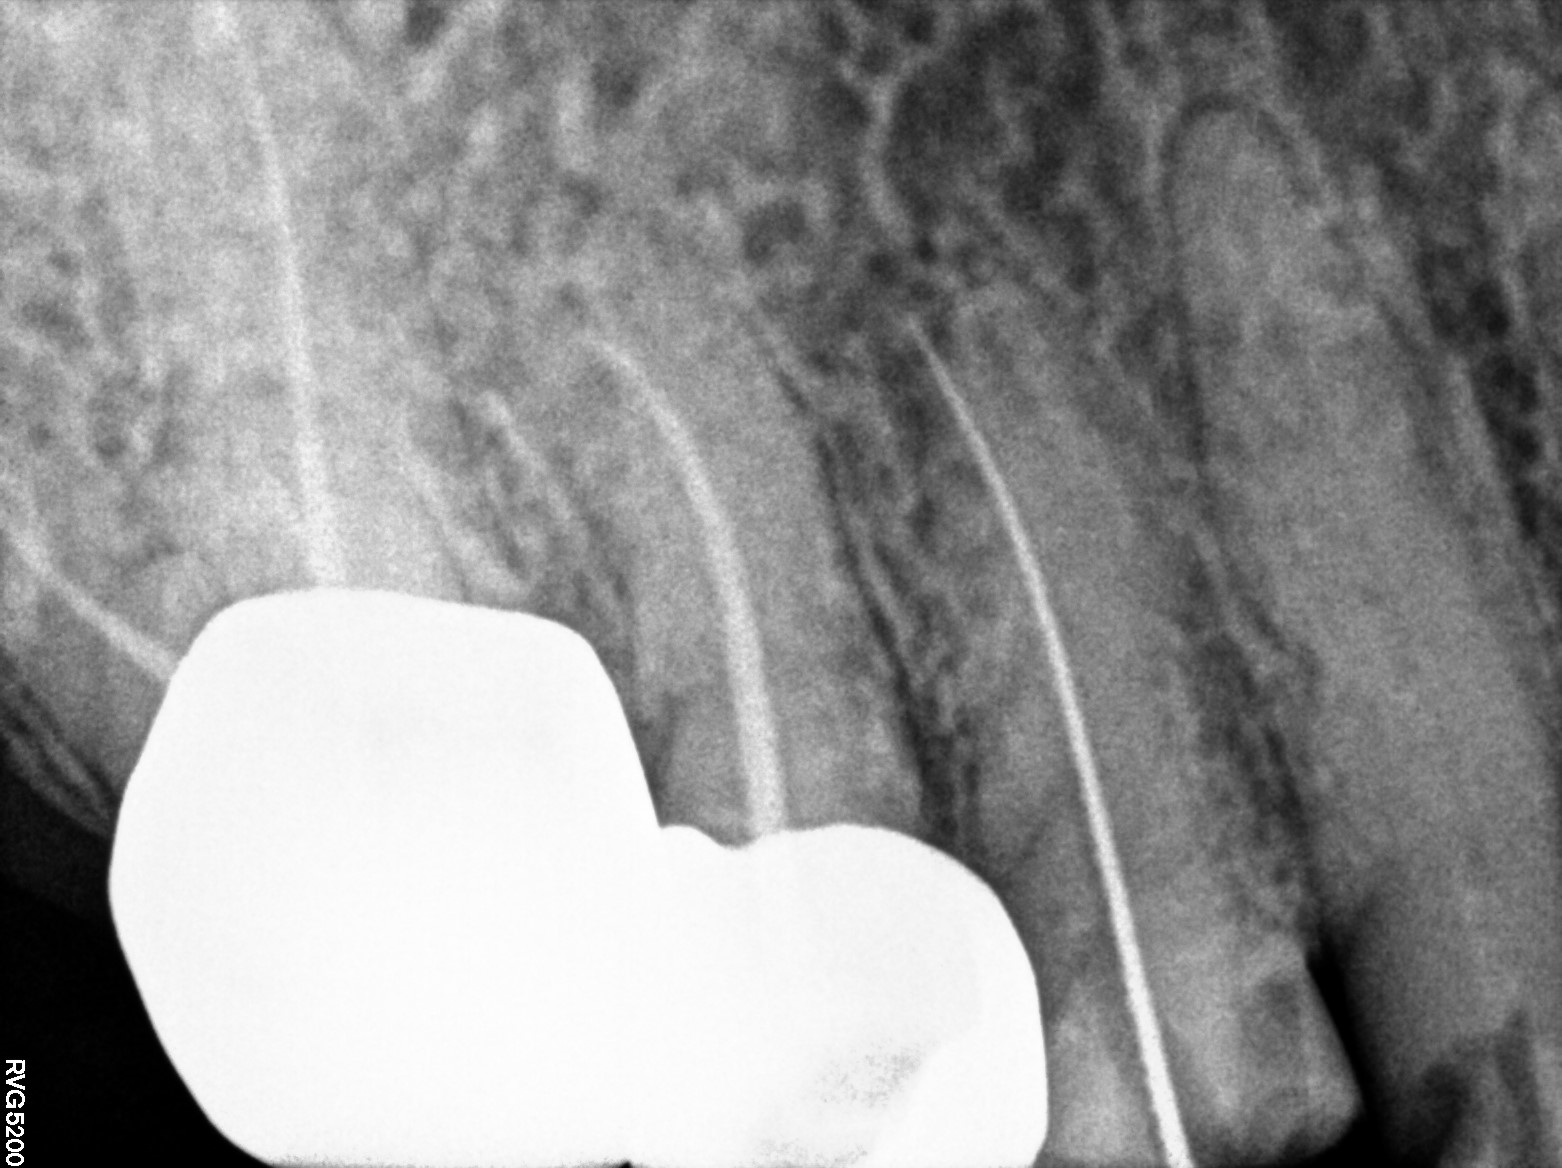

Dental Radiographs FHIR: DocumentReference · LOINC 24641-7

xray_1772525715_0.jpg

24641-7